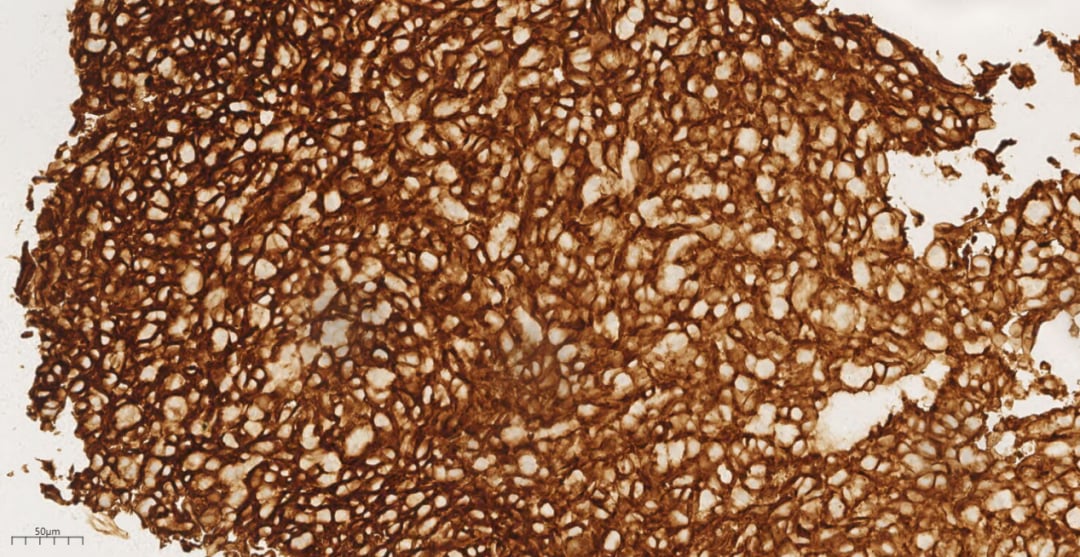

免疫组化结果显示,肿瘤细胞Vimentin(+)证实为间叶来源;CD31(+)、CD34(+)、F8(+)则明确了其血管源性肿瘤的性质。同时,CK(-)、D2-40(-)、Desmin(-)、Dog-1(-)、S-100(-)、SMA(-)等阴性结果排除了上皮来源肿瘤(如转移癌、非小细胞肺癌)、间皮瘤、淋巴管来源、平滑肌来源、胃肠道间质瘤等。Ki67(60%+)的高表达提示肿瘤增殖活性极强。这些免疫表型特征有力支持了肺的转移性肝血管肉瘤的诊断。

图7 免疫组化示肿瘤细胞CD31(+)

图8 免疫组化示肿瘤细胞CD34(+)

图9 免疫组化示肿瘤细胞F8(+)

图10 免疫组化示肿瘤细胞Ki67(60%+)